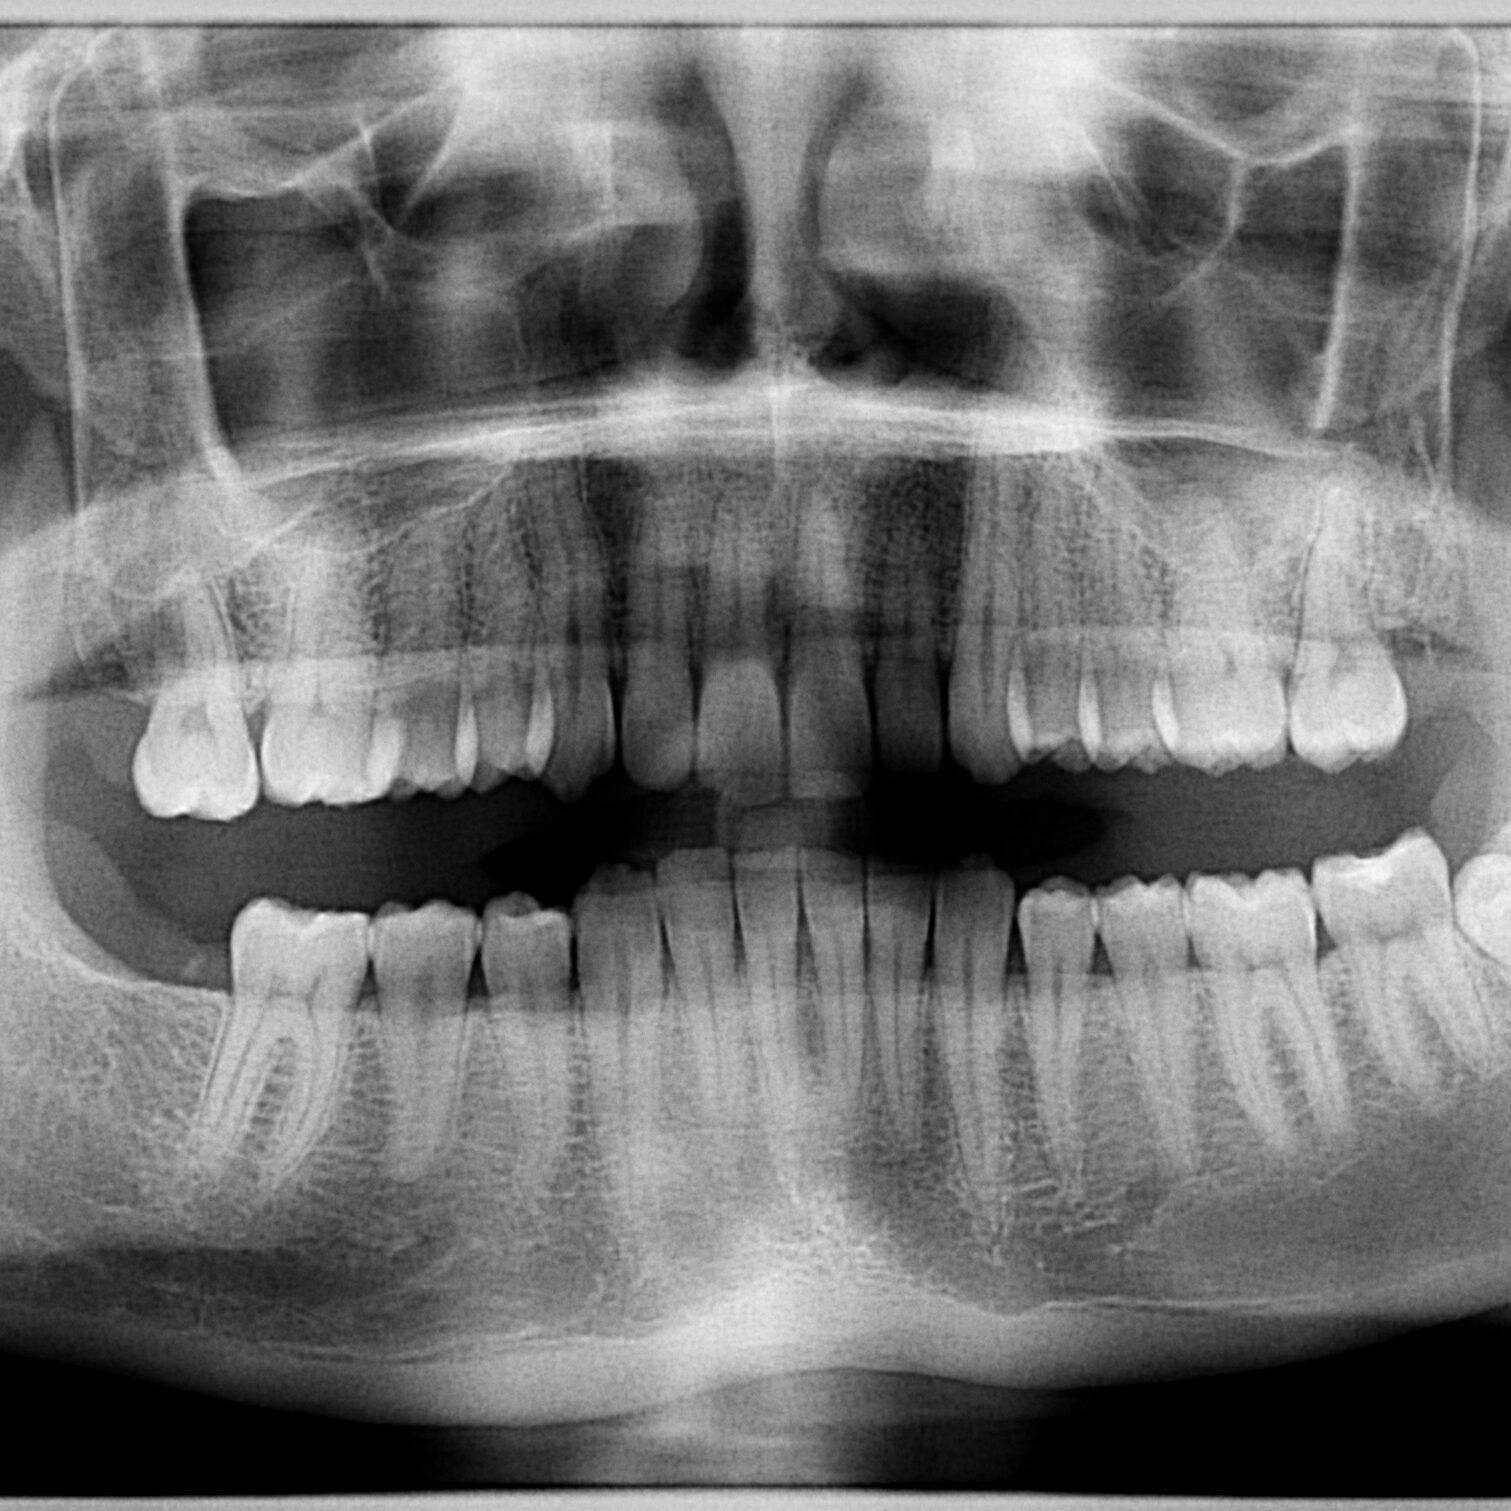

Orthopantomogram

X-ray panoramic two-dimensional image of the jaw that enables quick and easy diagnosis of almost all dental problems.

In addition to the classic orthopantomogram, a bitewing scan and scans of the maxillary sinuses and temporomandibular joint are also available.